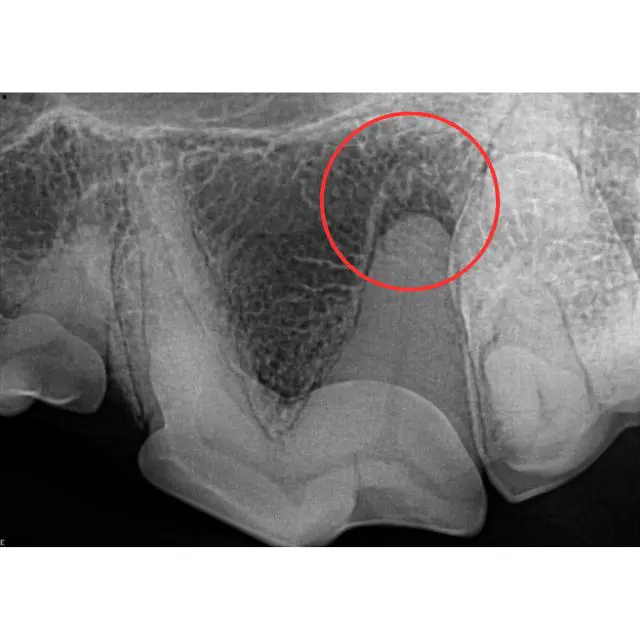

Radiograph of an uncomplicated crown fracture that has endodontic disease (see red circle). This tooth either requires root canal therapy or surgical extraction

Tooth fracture that is involving dentin exposure but not pulp cavity (uncomplicated crown fx)